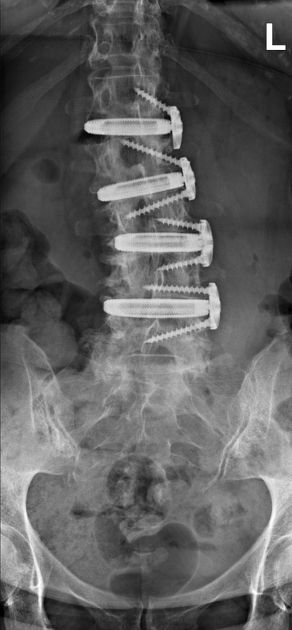

4. Hardware Failure or Fusion Issues

XLIF surgery relies on hardware like cages, screws, and rods to stabilize the spine while the bones fuse.

- Hardware Malposition or Failure: In some cases, the hardware can shift, break, or become loose. This may require a second surgery to correct or replace the components.